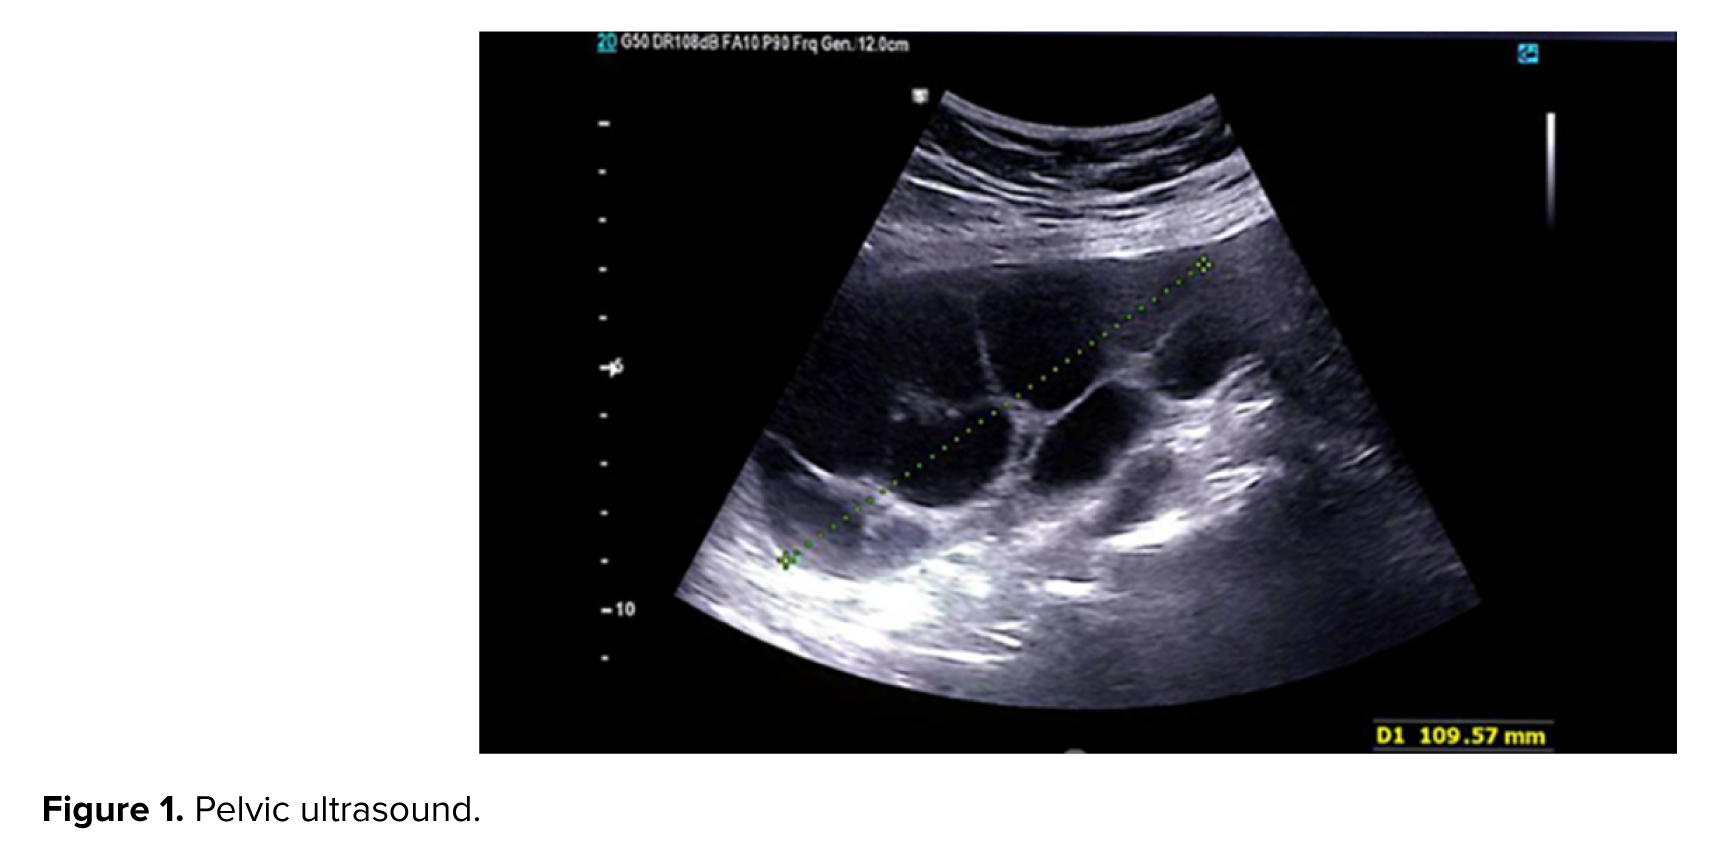

The patient conceived through IVF treatment after 10 yr of secondary infertility. According to history, on December 18, 2024, IVF was performed using 2 3-day frozen embryos. 4 wk later, the beta human chorionic gonadotropin (β-hCG) titer was 726. On January 20, 2025, at a gestational age of 10 wk, the case presented with an ultrasound showing an echogenic mass measuring 107 mm and 63 mm in the posterior part of the gestational sac, with abundant fibrocystic areas, indicating an incomplete mole or placental mesenchymal dysplasia, and a human chorionic gonadotropin hormone titer of 40,000. After initial investigations, tests (complete blood count, blood group Rh, liver function test, thyroid function tests, blood urea nitrogen, creatinine) and chest X-ray were requested and performed. The results of which were normal. Ultrasound-guided suction curettage was performed, and 48 hr later the initial suction curettage, a β-hCG titer was sent (the result of the β-hCG titer was 19120). A pelvic ultrasound was also performed. The ultrasound report included the following: observation of a heterogeneous structure measuring 20 and 14 mm in the endometrial fundus in favor of retained products of conception, some free fluid around the ovaries, and several ovarian cysts, the largest of which were 50 and 40 mm (Figure 1).